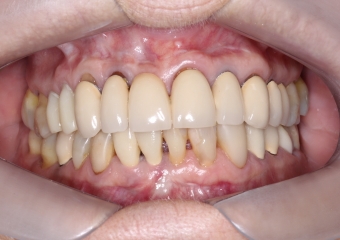

Foto intra oral frontal inicial